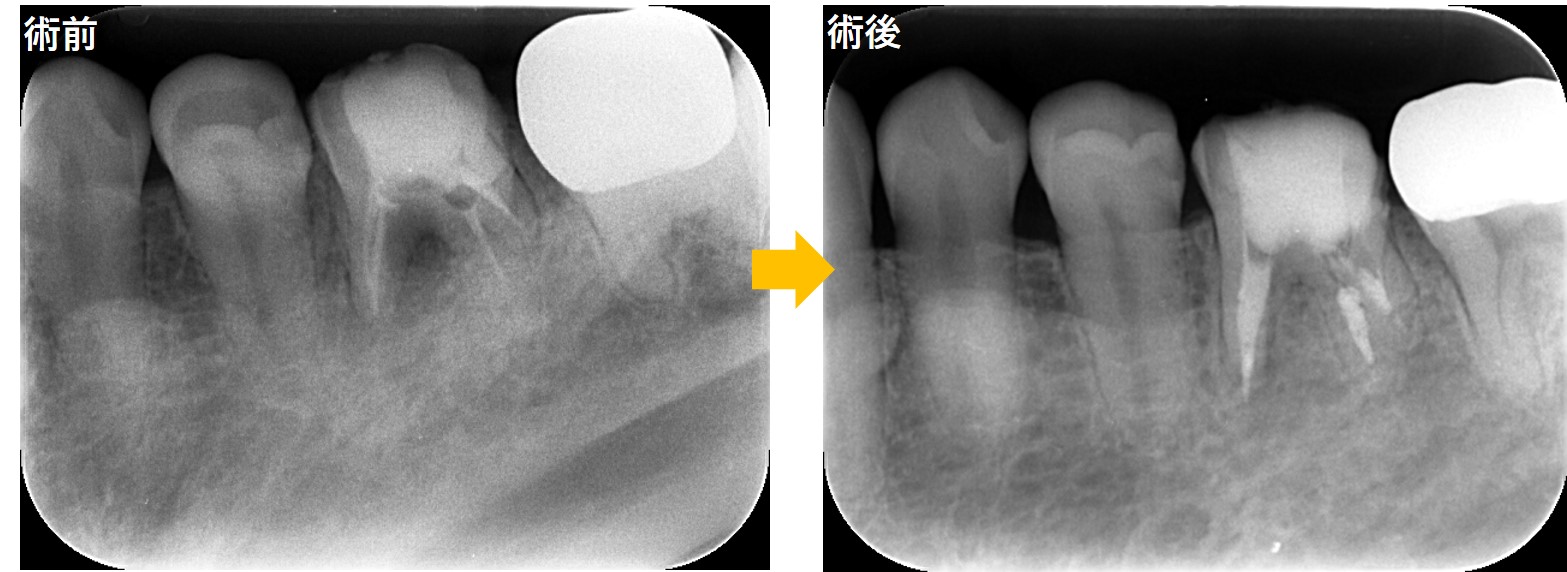

← 192.根分岐部(根と根の間)の歯周病?